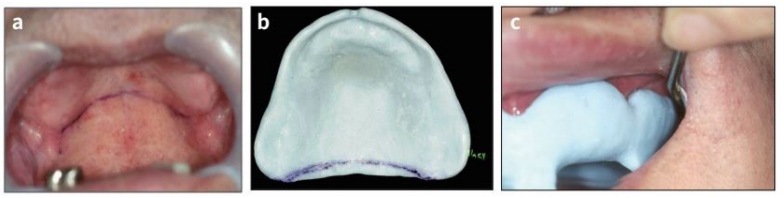

환자가 입을 반쯤 다물게 하고 border에 공기가 들어가도록 하기 위해 입을 위로 올리고 트레이를 아래 방향으로 힘 을 주어 구강 내에서 제거한다. 구강내에서 제거한 후 상악 인상체를 검사한다. 구강내에서 제거된 인상체는 필요한 해부학 구조가 나와 있는지 확인한다.

즉 순협측 vestibular reflection은 알맞게 기록되어야 한다. 인상면은 매끈하고 주름이나 흠이 없어야 한다. 또한 hamular notch와 vibrating line을 포함한 palate가 기록되어야 한다. Palate의 bibrating line을 확인 후 인상체에 표시해 준다(그림 25).